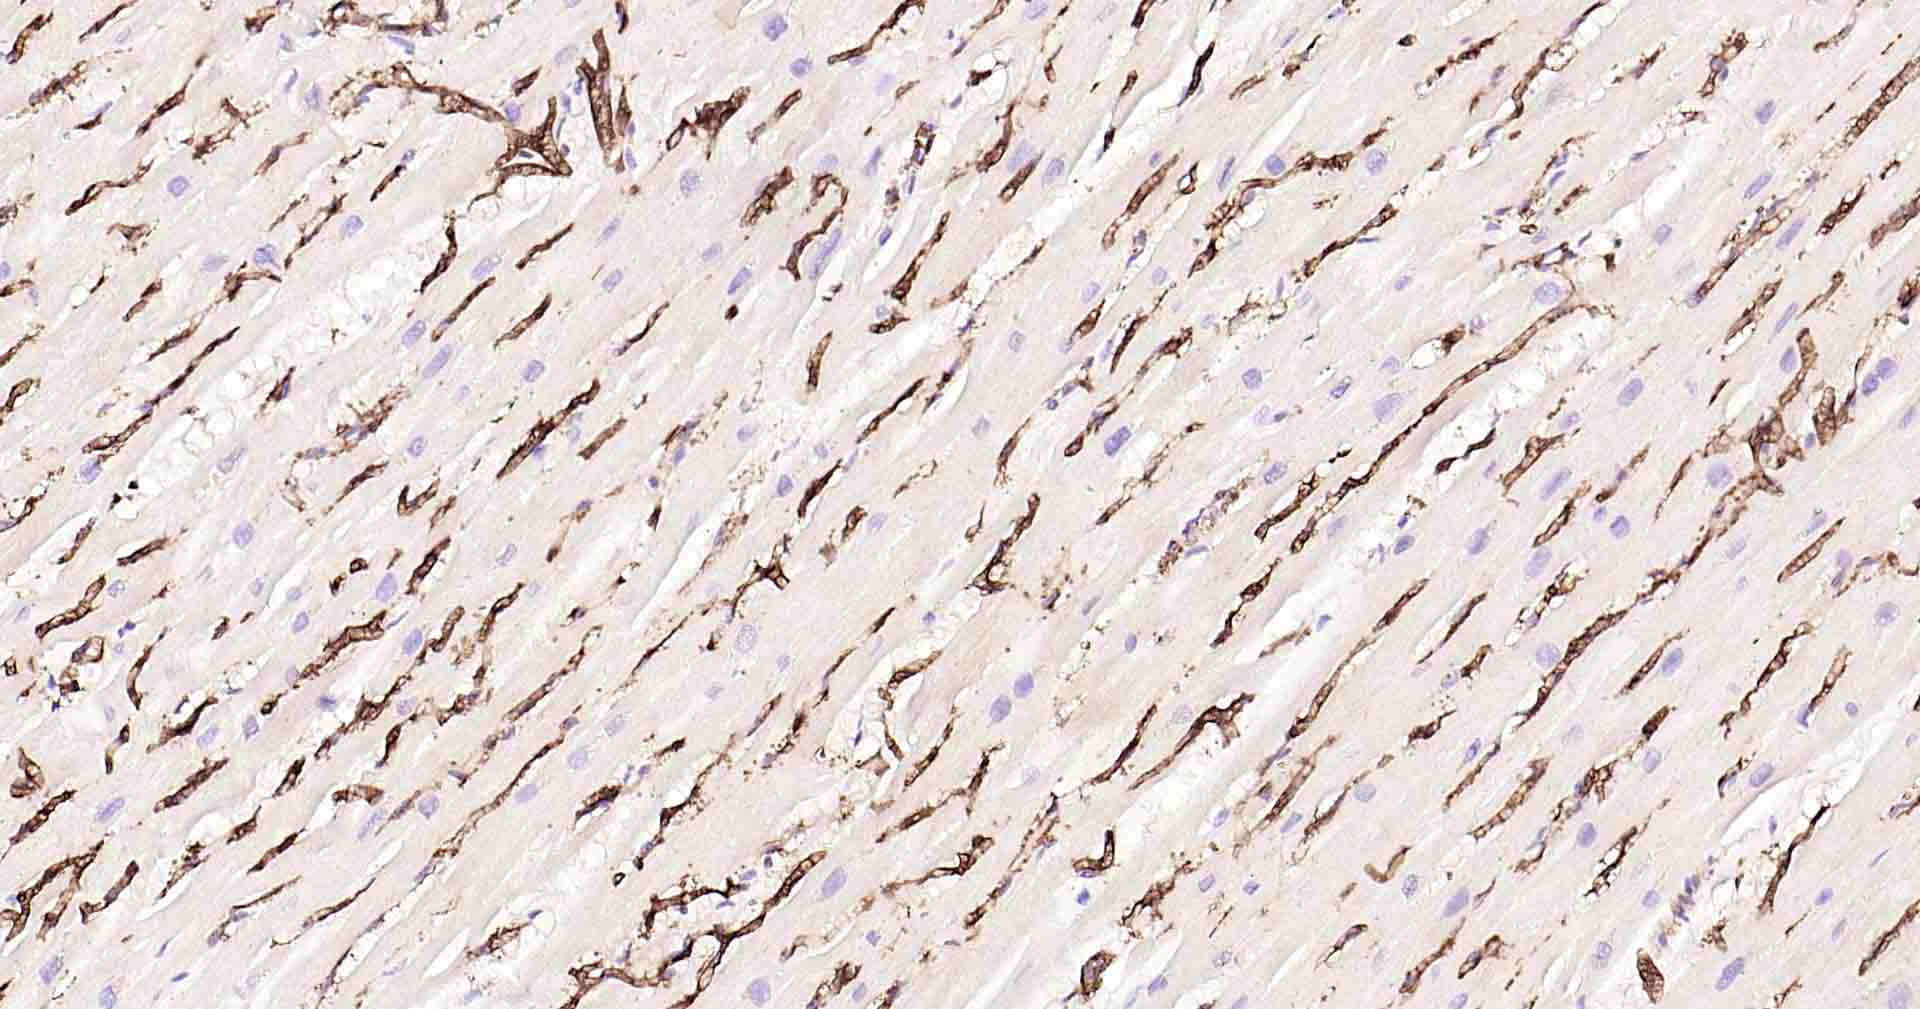

Paraformaldehyde-fixed, paraffin embedded Human Heart; Antigen retrieval by boiling in sodium citrate buffer (pH6.0) for 15 min; Antibody incubation with AQP1 Monoclonal Antibody, Unconjugated(bsm-52909R) at 1:200 overnight at 4°C, followed by conjugation to the SP Kit(Rabbit, SP-0023) and DAB (C-0010) staining.

Paraformaldehyde-fixed, paraffin embedded Rat Heart; Antigen retrieval by boiling in sodium citrate buffer (pH6.0) for 15 min; Antibody incubation with AQP1 Monoclonal Antibody, Unconjugated(bsm-52909R) at 1:200 overnight at 4°C, followed by conjugation to the SP Kit(Rabbit, SP-0023) and DAB (C-0010) staining.

Paraformaldehyde-fixed, paraffin embedded Mouse Heart; Antigen retrieval by boiling in sodium citrate buffer (pH6.0) for 15 min; Antibody incubation with AQP1 Monoclonal Antibody, Unconjugated(bsm-52909R) at 1:200 overnight at 4°C, followed by conjugation to the SP Kit(Rabbit, SP-0023) and DAB (C-0010) staining.